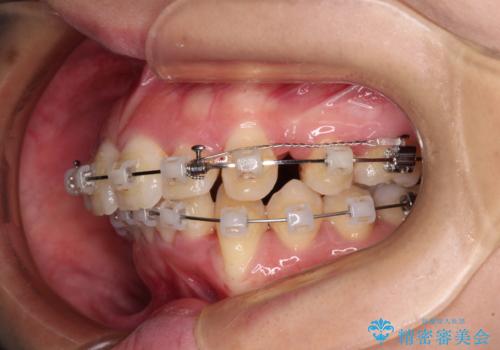

- クリアブラケット

舌の突出癖が顕著で、上顎歯列は完全なV字型となっている状態でした。

下顎歯列にも八重歯があり、上下左右の第一小臼歯4本を抜歯して、ワイヤー装置にて矯正治療を行うこととしました。